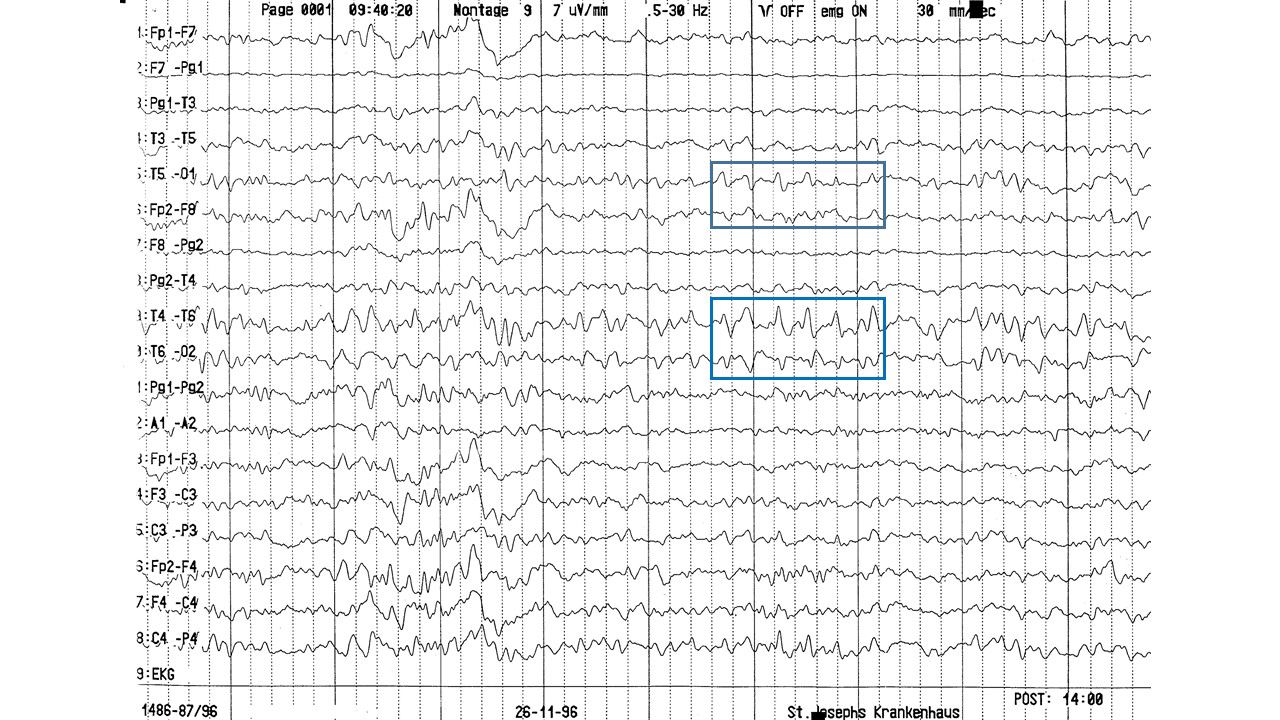

EEG-Seminar II | 38.59 zurück | weiter

folie88.jpg